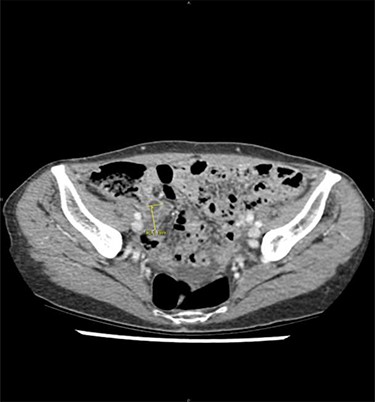

At clinical examination, abdominal pain was localized at the McBurney area, without signs of peritonitis; intestinal transit was preserved. Laboratory results showed a C-reactive protein at 2.1 mg/dl (N<1), white blood cells at 15 000 μl/m3 (N<10 000) and no liver or renal function tests alteration. On abdominal CT, a dilated appendix (12 mm) was observed with wall thickening and periappendiceal fluid, suggesting acute appendicitis (Fig. 1). An emergency appendicectomy was therefore indicated. At laparoscopic exploration, an inflamed appendix was observed as well as multiple and unexplained nodules, including an indurated lesion on the appendix. Appendicectomy was performed by ligation of the appendicular basis, and some peritoneal nodules were harvested. The postoperative course was uneventful.

Acute appendicitis on abdominal computed tomodensitometry (yellow arrow), characterized hereby by a dilatation of the appendicular lumen (12 mm) with wall thickening.